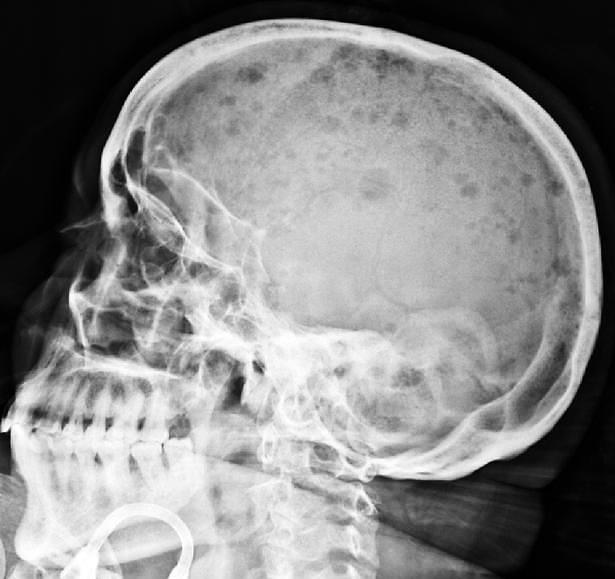

- sítios mais comuns: crânio, vértebras, costelas (ossos axiais), pelve, fêmur, clavícula, escápula; - neoplasia osteolítica (ativadora de osteoclastos, inibidora de osteoblastos), progride da cavidade medular aos tecidos periosteais; - a destruição óssea (hipercalcemia) promove dor e favorece fraturas patológicas.

Lesões osteolíticas à radiografia (setas), ao exame macroscópico do crânio e à dissecção da coluna vertebral, no mieloma múltiplo.